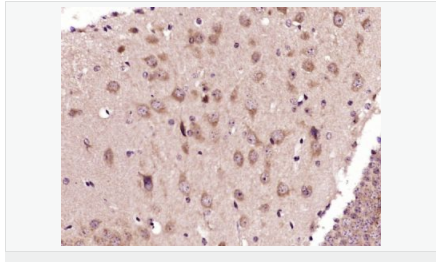

| 產(chǎn)品應(yīng)用 | WB=1:500-2000 IHC-P=1:100-500 IHC-F=1:100-500 Flow-Cyt=3ug/test ICC=1:100-500 IF=1:100-500 (石蠟切片需做抗原修復) not yet tested in other applications. optimal dilutions/concentrations should be determined by the end user. |

| 產(chǎn)品介紹 | This gene encodes an adenosine receptor that is a member of the G protein-coupled receptor superfamily. This integral membrane protein stimulates adenylate cyclase activity in the presence of adenosine. This protein also interacts with netrin-1, which is involved in axon elongation. The gene is located near the Smith-Magenis syndrome region on chromosome 17. [provided by RefSeq, Jul 2008]. Function: Receptor for adenosine. The activity of this receptor is mediated by G proteins which activate adenylyl cyclase. Subcellular Location: Cell membrane; Multi-pass membrane protein. Similarity: Belongs to the G-protein coupled receptor 1 family. SWISS: P29275 Gene ID: 136 Database links: Entrez Gene: 136 Human Omim: 600446 Human SwissProt: P29275 Human Unigene: 167046 Human Important Note: This product as supplied is intended for research use only, not for use in human, therapeutic or diagnostic applications. |